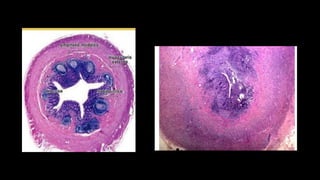

Etiologia

• Apéndice es un órgano linfoide que secreta moco

continuamente hacia el ciego.

• Obstrucción de la luz apendicular en la casusa del

Etiologia • Apéndice esun órgano linfoide que secreta moco continuamente hacia el ciego. • Obstrucción de la luz apendicular en la casusa del inicio de la inflamación, provocando estasis del moco, colonización bactriana, inflamación de la pared visceral, oclusión de los vasos sanguíneos y necrosis del área • Inflamación irrita el peritoneo y causa el dolor abdominal

Causas que determinanel proceso obstructivo: • Hiperplasia de folículos linfoides 60%. • Fecalitos 35% • Cuerpos extraños • Tumores 1%